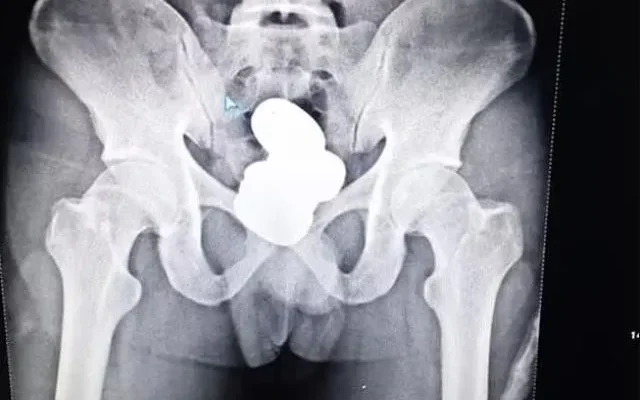

Güvenlik güçleri tarafından gözaltına alınan Mohammad Sharif isimli şahsın makatında dört kapsül haline getirilmiş 850 gram ağırlığında toz altın bulundu.